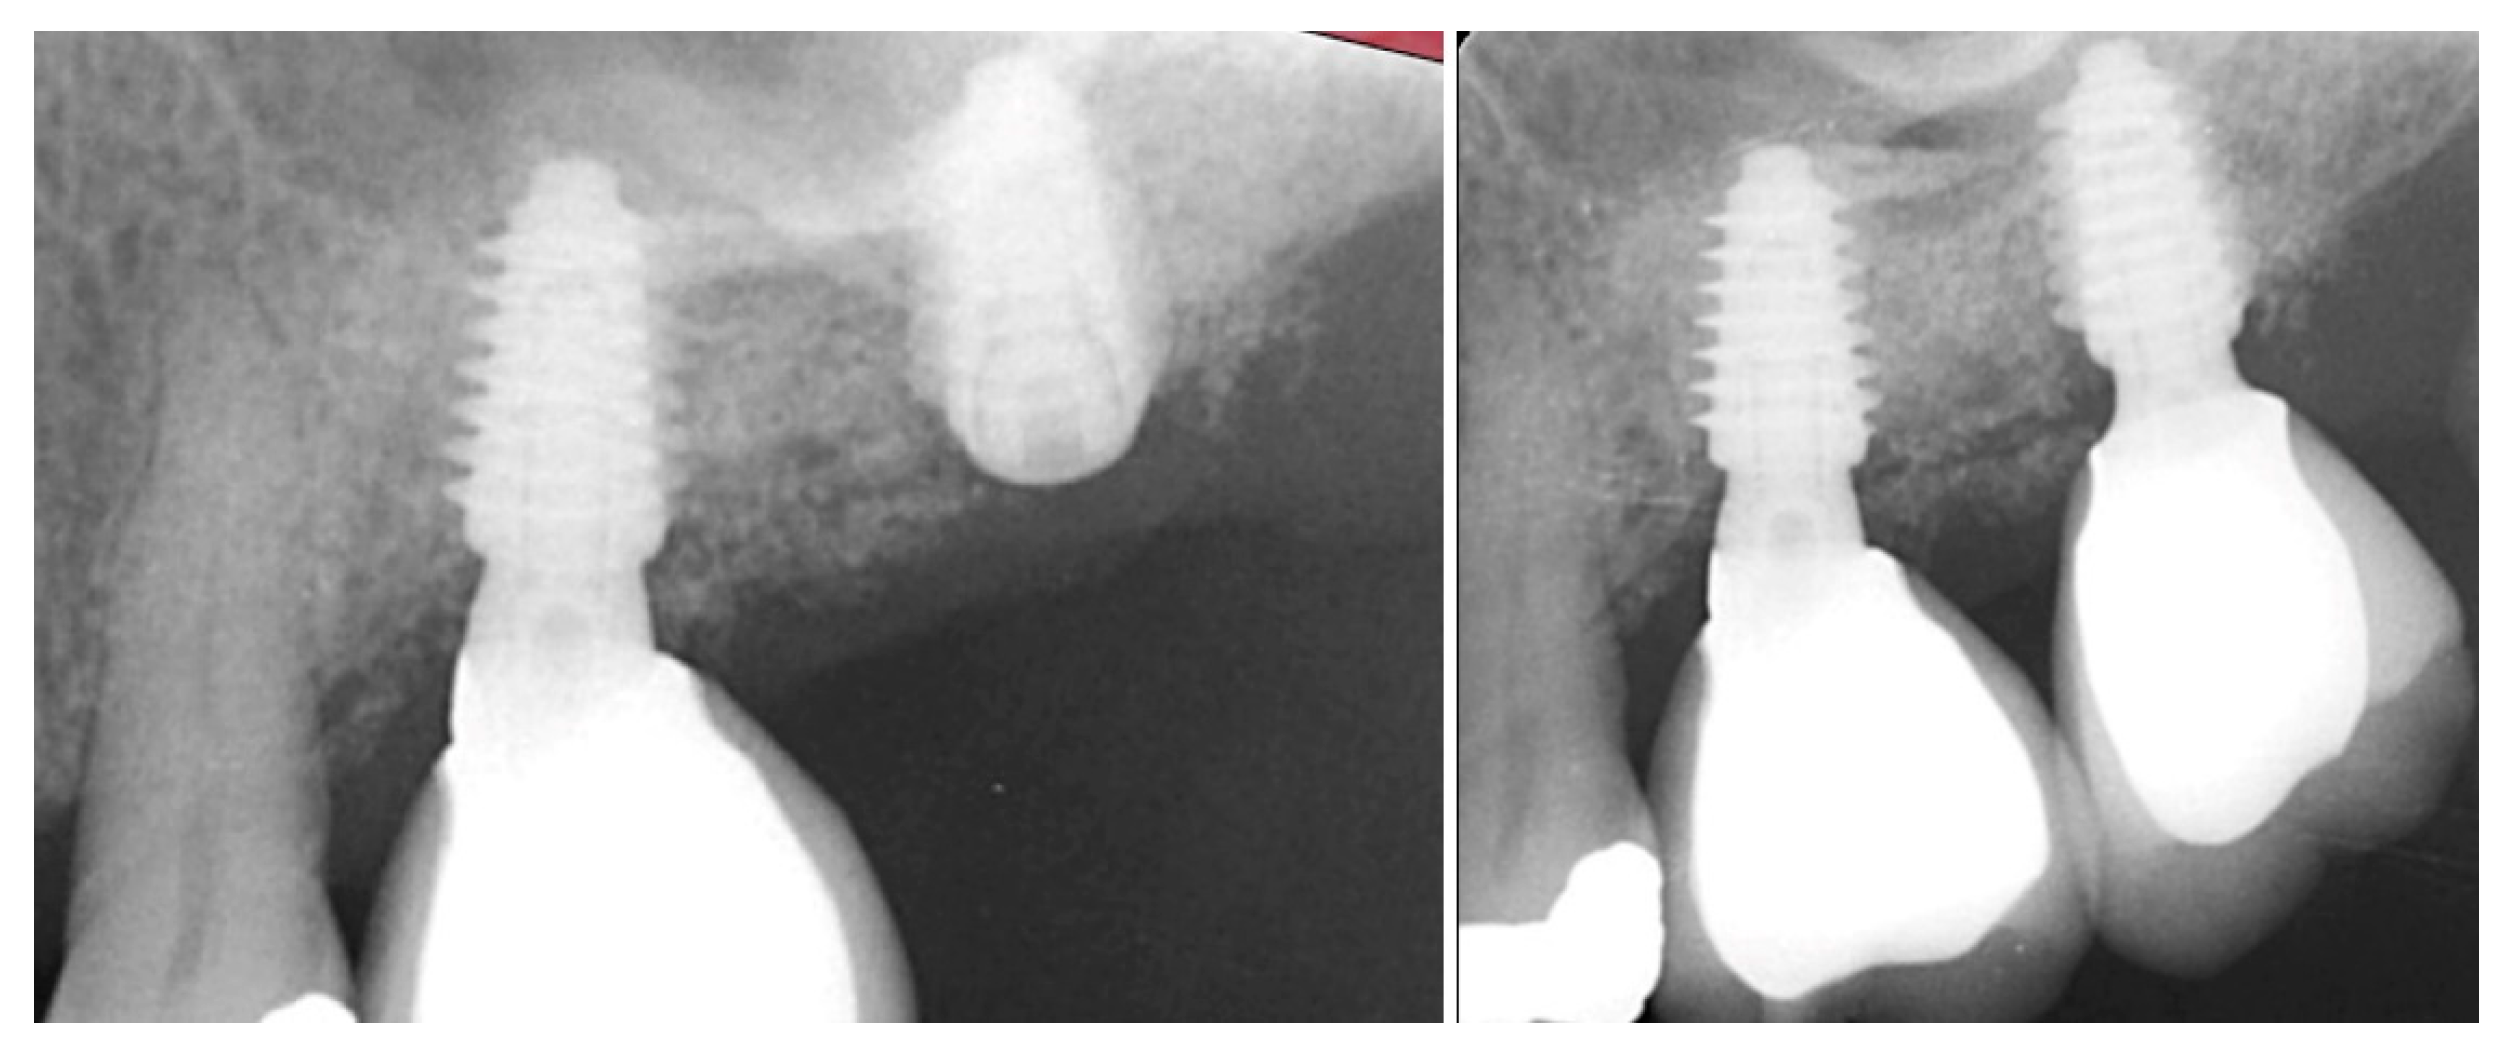

The patient returned at 10 weeks and a radiograph was obtained to evaluate the height of the crest (Figure 15 right). A crestal sinus lift was performed following the previous steps described in case 1 and 2 and a 4 × 8.5 mm Anyridge implant was placed with a cover screw.

The patient returned at 10 weeks and the implant was uncovered. An impression was obtained, and a healing abutment placed on the site. A radiograph was obtained to verify the healing abutment was seated, which demonstrated conversion of the graft material to immature host bone (Figure 16, right). The restoration was returned from the lab and the patient was returned to complete the treatment. The healing abutment was removed (Figure 17, left) and the restoration was inserted (Figure 17, middle). A radiograph was obtained to verify complete seating of the restoration to the implant (Figure 17, right). Radiographically, the previously grafted area at the crest and sinus blended well with the surrounding host bone.

Figure 16.

Radiograph following crestal sinus augmentation with EthOss and implant placement (left) and at uncovery and healing abutment placement after 10 weeks of implant placement demonstrating conversion of the graft material to host bone (right).

Figure 17.

Healing abutment removal demonstrating noninflamed keratinized tissue over the grafted area (left), placement of the screw retained restoration (middle) and a radiograph to verify mating of the restoration to the implant at the connector (right).